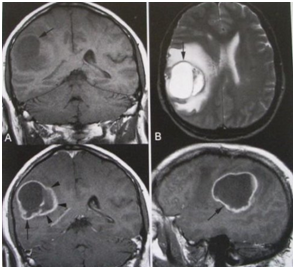

MRI增强扫描,胶质母细胞瘤实质呈环形强化

脑胶质瘤治疗前后对比